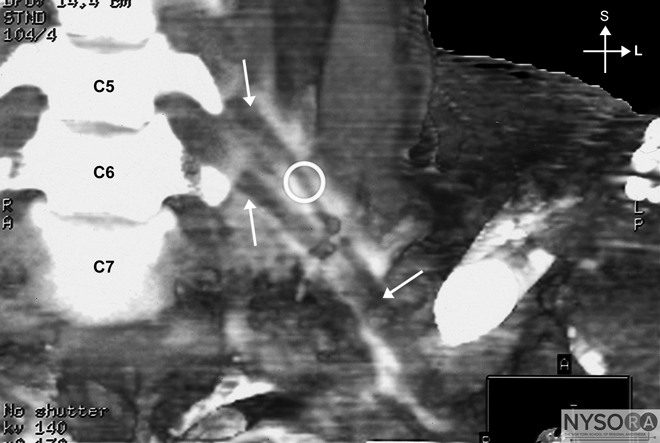

Figure 7: Needle insertion for interscalene brachial plexus block. The needle is inserted between fingers posi- tioned in the interscalene groove with a slight caudad ori- entation to decrease the chance of entrance in the cervical spinal cord. White arrow: insertion of the sternal head of the sternocleidomastoid muscle. Red arrows: posterior border of the sternocleidomastoid muscle. Blue arrow: external jugular vein. The insertion point for the block is often immediately posterior to the external jugular vein. The needle must never be oriented cephalad; a slight caudal orientation reduces a chance for an inadvertent insertion of the needle into the cervical spinal cord. The nerve stimulator should be initially set to deliver 0.8 to 1.0 mA (2 Hz, 0.1 ms). The needle is advanced slowly until stimulation of the brachial plexus is obtained. This typically occurs at a depth of 1 to 2 cm in most all patients. Once appropriate twitches of the brachial plexus are elicited, 25 to 35 mL of local anesthetic are injected slowly with intermittent aspiration to rule out intravascular injection. This "low-interscalene" approach differs from the classic description of the interscalene block, which uses the cricoid cartilage as a landmark. The principal advantage to the low approach is that the brachial plexus is more compact at the lower levels, and reliable coverage of the upper, middle, and lower trunks can be achieved with a single injection (Figure 8). In contrast, the classic approach may spare the lower trunk, which limits its use for forearm and elbow surgery. When insertion of the needle does not result in upper extremity muscle stimulation, the following maneuvers can be used (Figure 9): 1. Keep the palpating hand in the same position and the skin between the fingers stretched 2. Withdraw the needle to the skin level, redirect it 15° posteriorly, and repeat the needle advancement. 3. Withdraw the needle to the skin level, redirect it 15° anteriorly, and repeat the needle insertion.

Figure 8: Distribution of the mixture of local anesthetic and a radiopaque contrast after an interscalene brachial plexus injection. The arrows and the circle indicate "negative" contrast image of the roots of the brachial plexus.